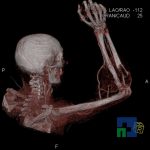

În cazul traumatismelor cranio-cerebrale:

- Diagnosticul edemului cerebral, a contuziei cerebrale, a leziunilor axonale difuze edematoase/hemoragice, a dilacerării cerebrale, a hematomului intraparenchimatos posttraumatic, a hematoamelor subdurale/extradurale (acute, subacute, cronice), a hemoragiei intraventriculare, a hemoragiei subarahnoidiene

- Diagnosticul traumatismelor de bază de craniu

- Diagnosticul fracturilor: